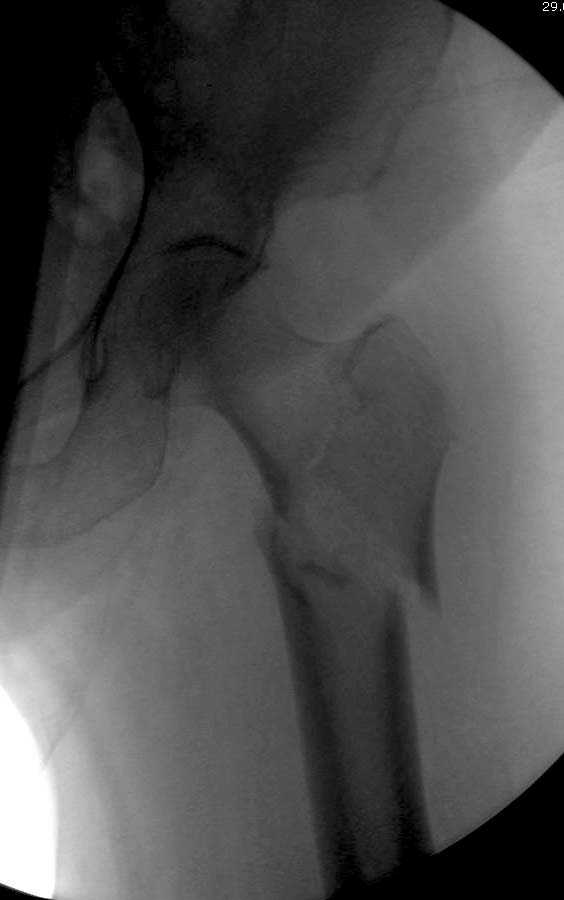

Здесь представлен случай, где в послеоперационном периоде обнаружена техническая ошибка, Gamma 3 установлен с нарушением методики. Больная в 91 лет, прооперирована через день после поступления и выписана через 48 часов.

При первом послеоперационном поликлиническом осмотре больная предъявила жалобы на боли в бедре. В серийных снимках обнаружен продольный перелом верхнего отдела бедра.

Считаем, что техническая ошибка произошла во время установки гвоздя, когда рассверливанию канала не уделили должного внимания. Канал остался узковат, и гвоздь был забит с силой. Полная нагрузка конечности приостановлена на две недели, и боли в конечности изчезли. Больная начала нагрузку и перелом срастается. -- Djoldas Kuldjanov, M.D. Associate Professor Department of Orthopedic Surgery St. Louis University